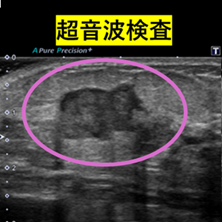

超音波検査は有用ですか?

デンスブレストの場合、マンモグラフィではしこりが乳腺に隠れて見えにくくなることがあります。

そのため、マンモグラフィと超音波検査を併用することで、より精度の高い診断が可能になります。 超音波検査は痛みもほとんどなく、体への負担も少ない検査です。

より安心して検診を受けていただくためにも、併用検査をおすすめしています。